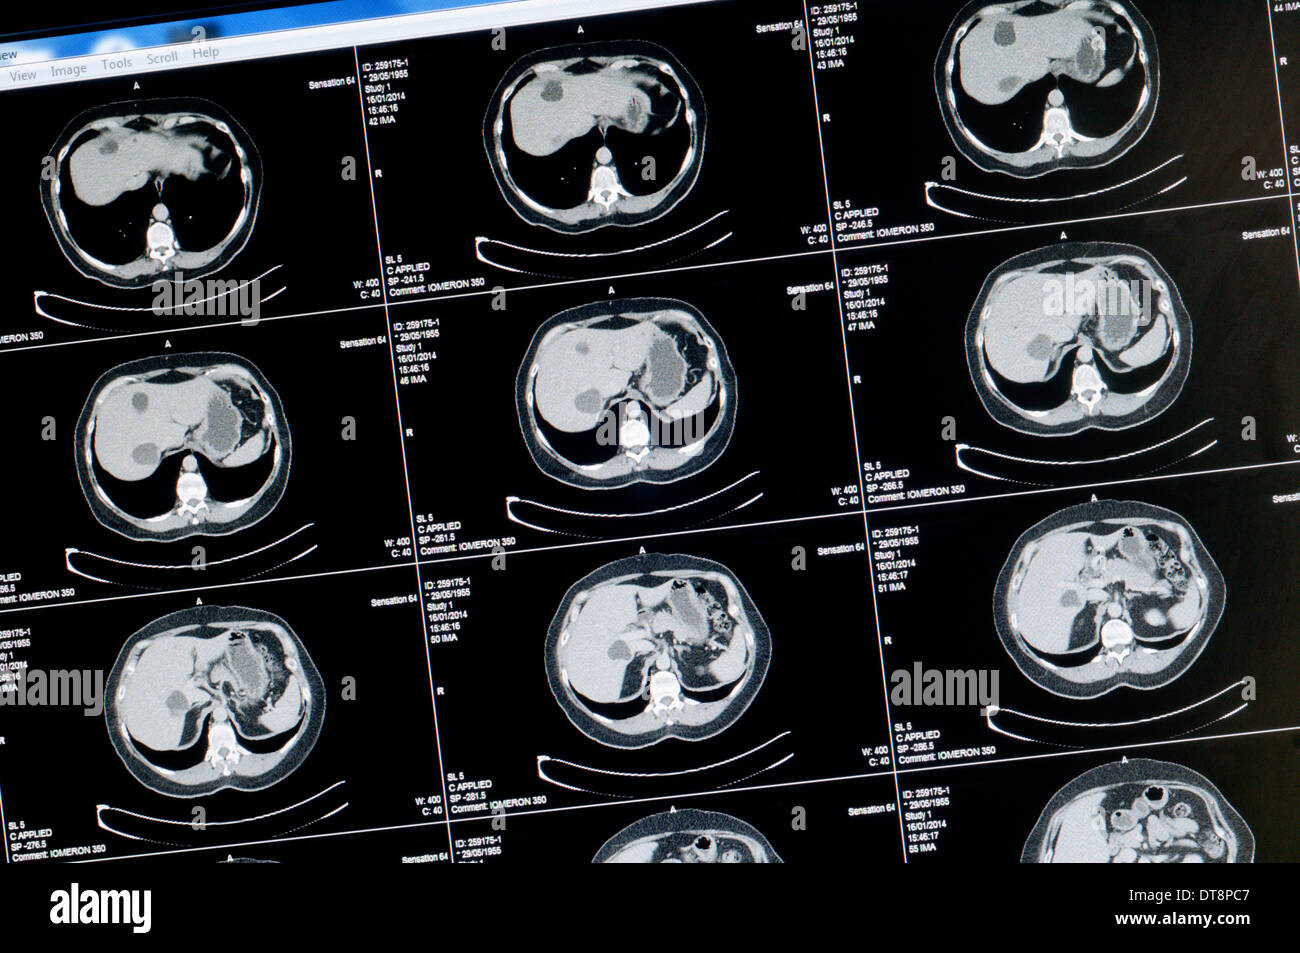

Scansione TC di sano 58 anno vecchia donna. NB: il testo è stato resi anonimi per preservare la privacy. Foto Stockhttps://www.alamy.it/image-license-details/?v=1https://www.alamy.it/scansione-tc-di-sano-58-anno-vecchia-donna-nb-il-testo-e-stato-resi-anonimi-per-preservare-la-privacy-image66576055.html

Scansione TC di sano 58 anno vecchia donna. NB: il testo è stato resi anonimi per preservare la privacy. Foto Stockhttps://www.alamy.it/image-license-details/?v=1https://www.alamy.it/scansione-tc-di-sano-58-anno-vecchia-donna-nb-il-testo-e-stato-resi-anonimi-per-preservare-la-privacy-image66576055.htmlRMDT8PC7–Scansione TC di sano 58 anno vecchia donna. NB: il testo è stato resi anonimi per preservare la privacy.